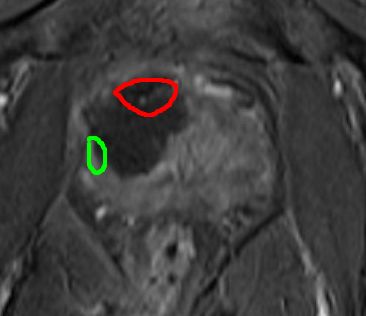

Post-surgery (and post MRI) consultation on 28 May 2014

Surgeon had already said the post-surgery MRI (one picture I sent him) looked good. This was an initial MRI scan, only 2½ weeks after my surgery. The one in November will give a better idea of the status of any remaining cancer.

Since then, he'd had an opportunity to look at the whole set of post-surgery MRI images.

He said that these preliminary images suggested that the significant cancer had been destroyed (ablated).

The ablated area extended significantly below where the anterior tumour had been (see annotated sketch - original tumour outlined in red).

Commenting on this, he said:

"The ice-ball (produced by the cryotherapy) would have done that". Basically, that's the best precision that could be achieved.

But an advantage may be that it may have also partially destroyed the peripheral 3 + 3 cancer on the right hand side, (marked as a green area). Even though I had asked him not to, the cryo could not be controlled precisely enough not to destroy that.